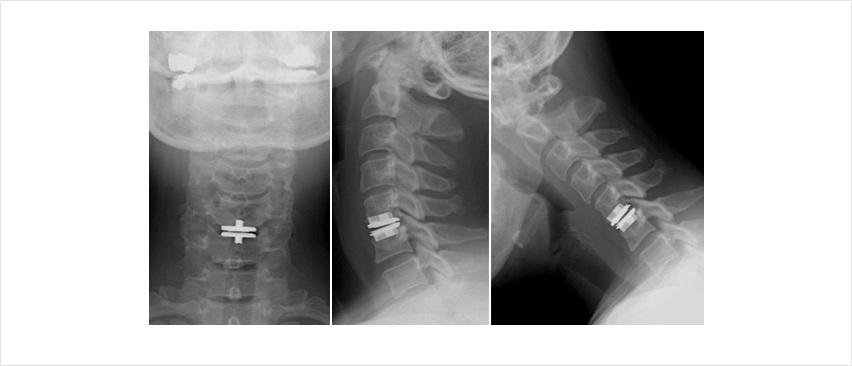

목 디스크의 수술 방법은 크게 4가지 수술법이 있습니다.